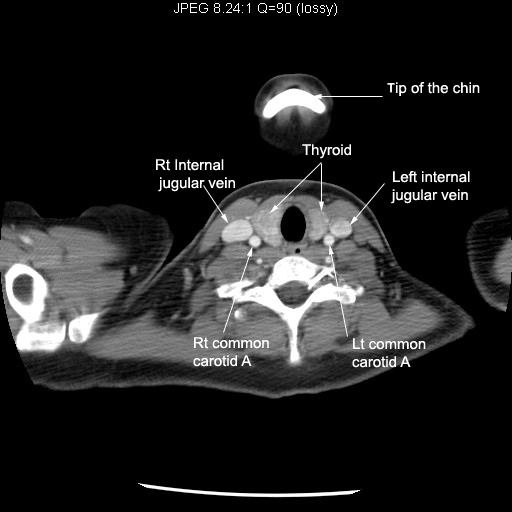

Identify the vascular structures. Click the image for labeling.